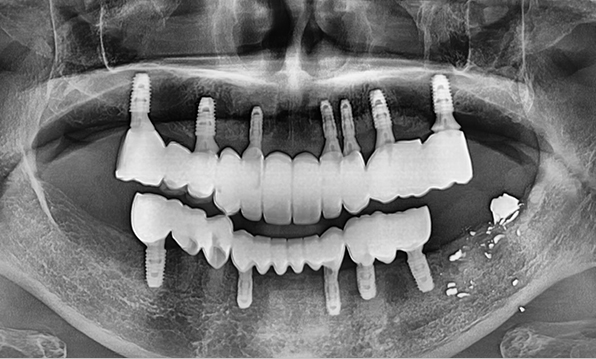

In full-mouth implant cases, implants are placed only where needed, and the remaining gaps are restored using a bridge (pontic) method — minimizing the total number of implants while achieving masticatory force comparable to natural teeth, helping to reduce the financial burden.